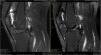

The Magnetic Resonance Imaging Protocol: routine 2D MRI exams were obtained from 12 PWH, using a 1.5- Tesla MRI system (Philips Achieva 1.5-T MRI System, Philips Medical Systems, Best, The Netherlands), totaling six knees and six ankles. The remaining patients were not examined owing to a series of logistic difficulties. Images were obtained before the RS, and 6 months after the procedure (Fig. 1).

Magnetic resonance imaging of a 33-year-old patient with haemophilic arthropathy of the knee. The T2-weighted SPIR (Spectral Presaturation with Inversion Recovery) image shows highly enhanced joint effusion. The hypertrophic synovium with black hemosiderin deposits is irregular with variable composition and different thicknesses along the articular surface (arrows). Adjacent soft tissues appear light grey (left). Magnetic resonance imaging obtained six months after treatment shows that the size of the synovium (arrow) and extent of joint effusion have both been reduced (right).